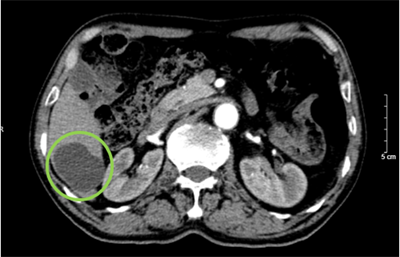

Điều trị ung thư đường mật bằng liệu pháp miễn dịch phối hợp hóa chất tại Bệnh viện Bạch Mai

Ngày đăng: 15/07/2025

Ung thư đường mật (UTĐM) là những tổn thương ác tính xuất phát từ tế bào biểu mô của đường mật, bao gồm: ung thư bóng Vater, ung thư túi mật, UTĐM trong gan và UTĐM ngoài gan. UTĐM có thể di căn ra...